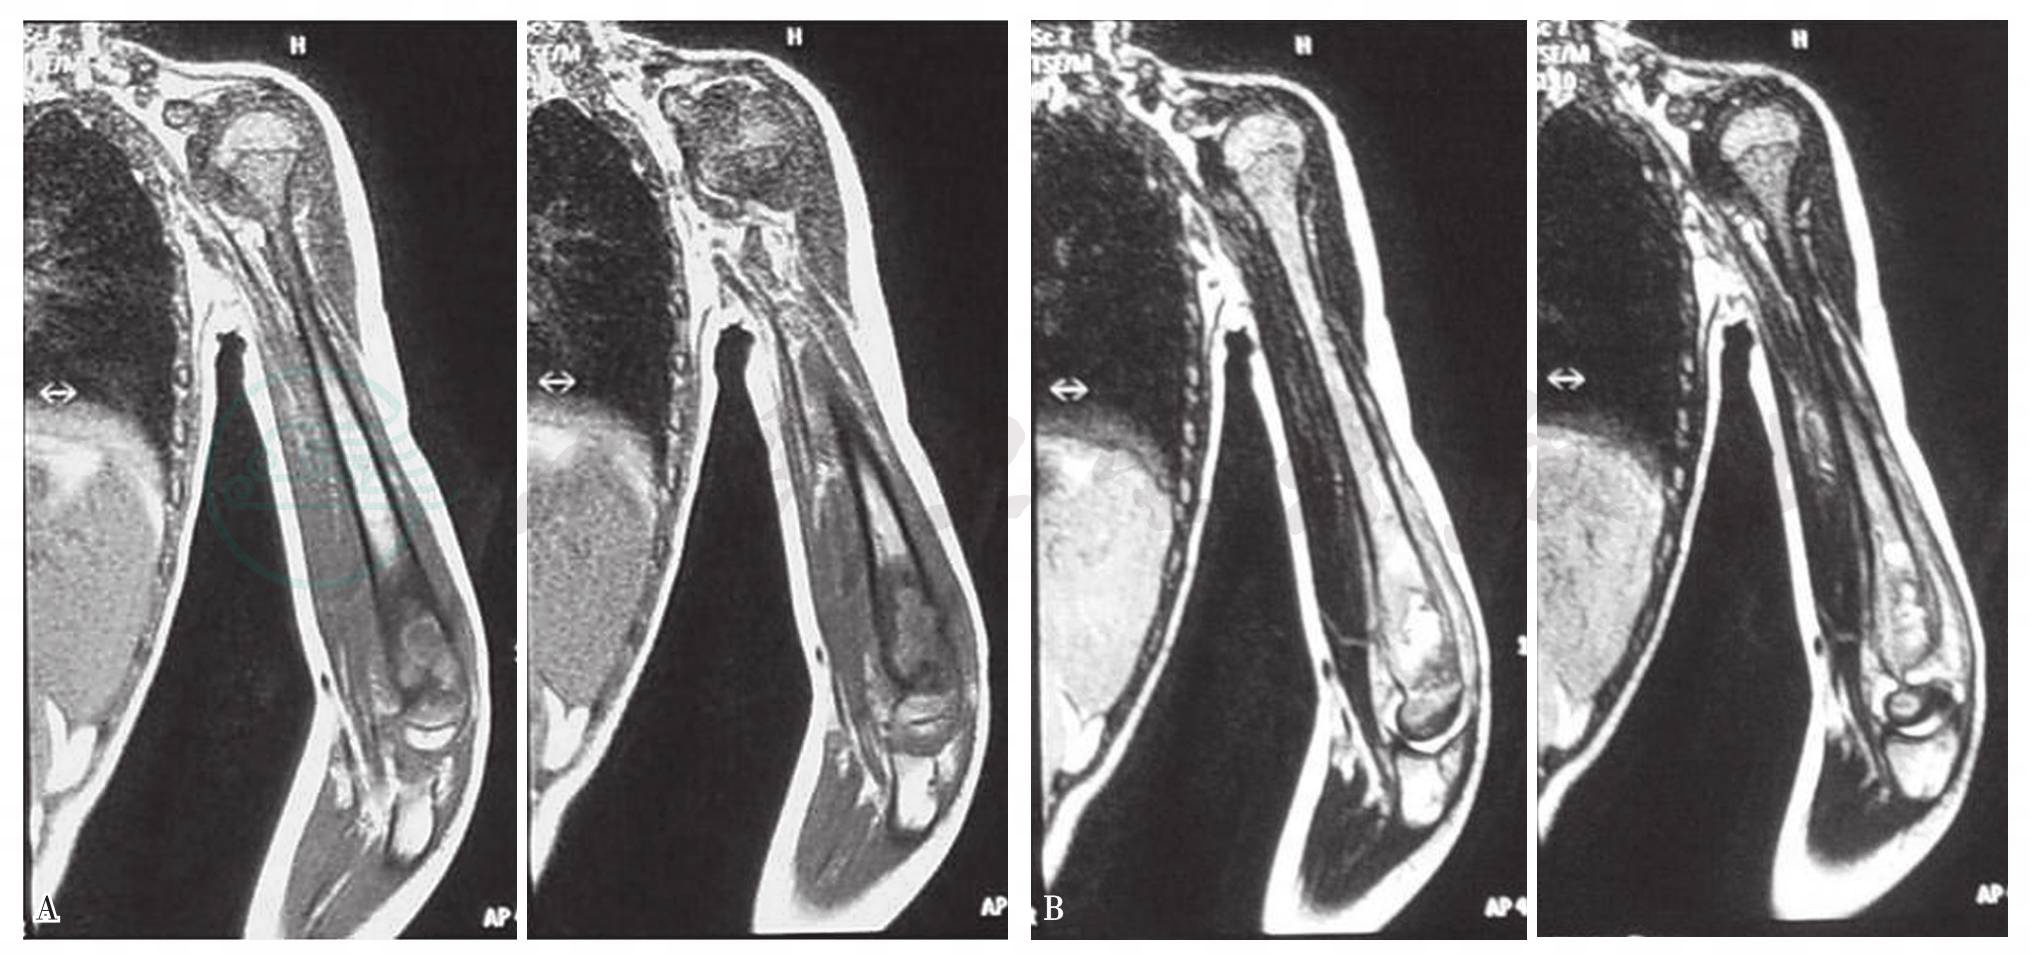

正常骨髓高信号为异常的骨髓水肿及骨质破坏信号取代。骨质破坏在T1加权像表现为骨质中低均一的低信号阴影,在T2加权像表现为骨质内高中低的混杂信号。骨髓水肿在T1加权像表现为稍低信号、T2加权像表现为近于骨髓信号的片状模糊影(图5~图8)。

图5 肱骨结核MRI

T1加权表现为稍低信号;T2加权表现为近于骨髓信号的片状模糊影